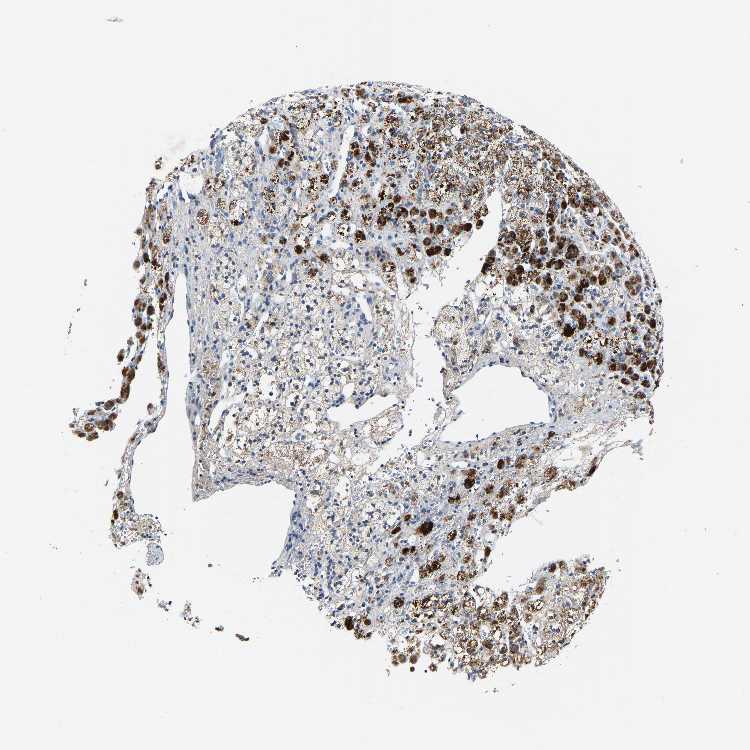

ADRENAL GLAND - Antibody stainingi

Antibody staining in the annotated cell types in the current human tissue is reported as not detected, low, medium, or high, based on conventional immunohistochemistry profiling in selected tissues. This score is based on the combination of the staining intensity and fraction of stained cells.

Each image is clickable and will lead to virtual microscopy that enables deeper exploration of all samples and also displays staining intensity scores, fraction scores and subcellular localization as well as patient and tissue information for each sample.

Antibody HPA020381

Glandular cells Medium